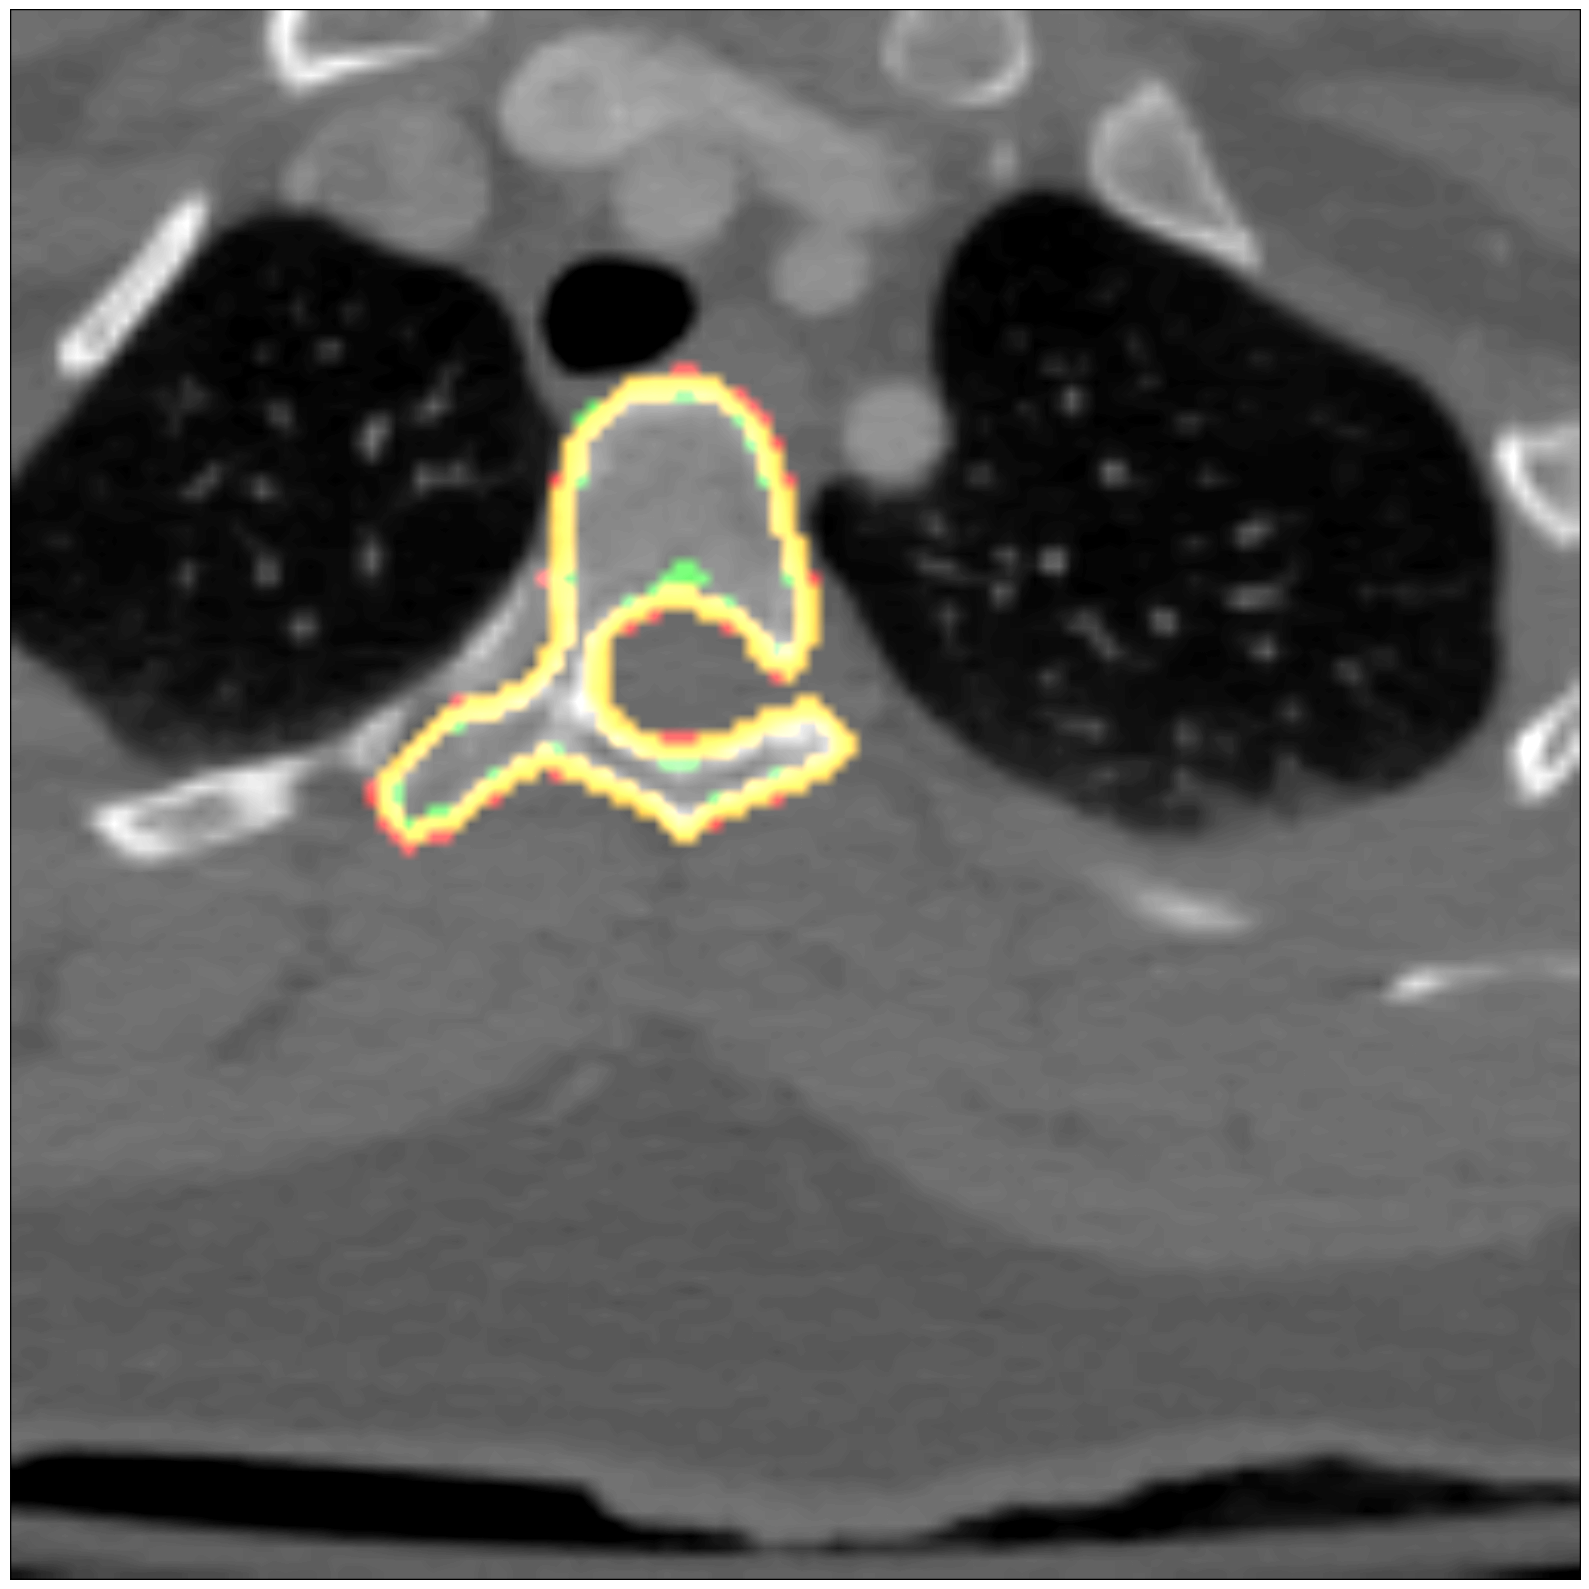

Some segmentation results at different vertebrae (top) and liver (bottom) areas are depicted in Fig. 2. The red contour corresponds to the outline of the prediction, green to the ground-truth and yellow to the overlap of the outlines.